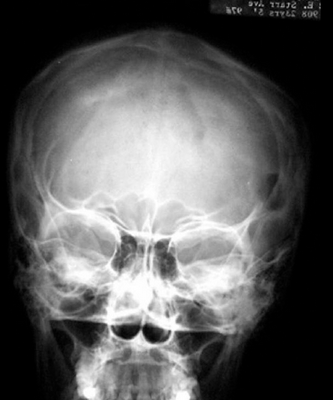

На рентгеновских снимках эозинофильная гранулема имеет вид литического очага округлой или овальной формы с четкими границами, расположенного преимущественно в костномозговой полости. При этом его размеры могут варьироваться в широких пределах. Как правило, признаки перифокального склероза отсутствуют. При поражении губчатой кости наблюдается так называемый пробойниковый дефект, а при локализации в позвоночнике может наблюдаться клиновидная деформация или формирование плоского позвонка. Таким образом, рентгенологическая картина при эозинофильной гранулеме не имеет специфических черт и во многом схожа с саркомой Юинга, остеогенной саркомой и другими злокачественными образованиями.

Использование различных методов визуализации (рентгенография, КТ, МРТ) позволяет выявить очаги деструкции величиной до 5 см с четкими границами без склеротических изменений, иногда — патологические переломы, уплощение пораженных позвонков (vertebra plana).

- Рентгенография костей. При рентгенологическом исследовании определяются единичные или множественные опухолевидные образования, участки деструкции, которые могут располагаться как в трубчатых, так и в плоских костях. При подозрении на эозинофильную гранулему обязательно проводят рентгенографию челюстей.